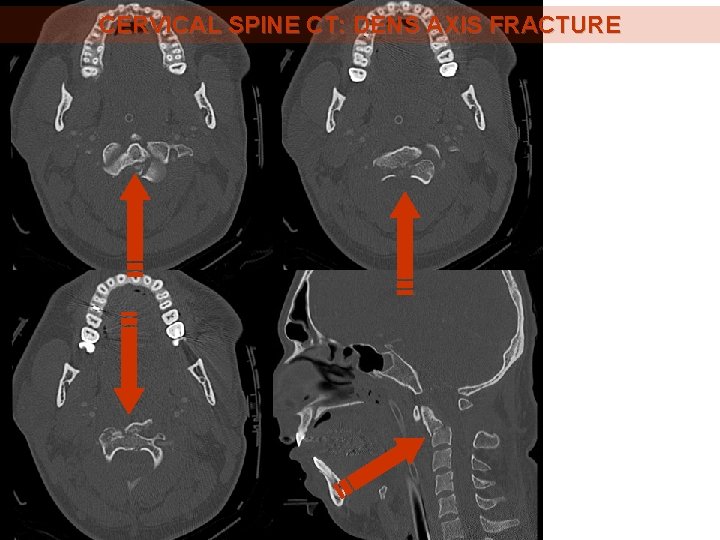

CERVICAL SPINE CT: DENS AXIS FRACTURE